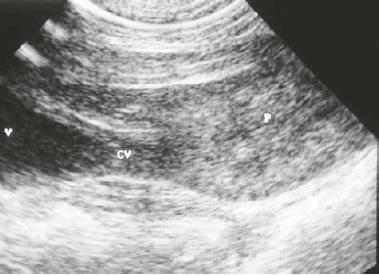

Nueva Imagen - ECOGRAFIA